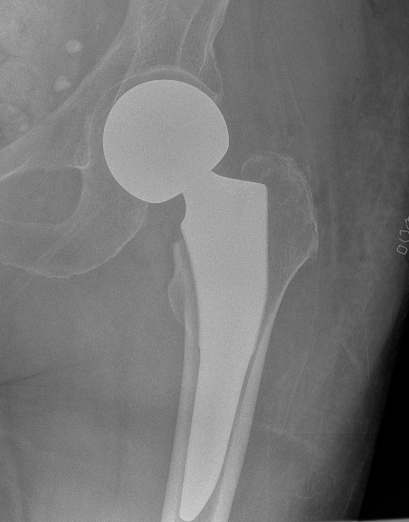

Cemented unipolar hemiathroplasty Uncemented bipolar hemiarthroplasty

Bipolar modular

Concept

- second articulation between inner smaller head and polyethylene liner

- reduce wears on acetabulum

- improved function and less pain

- may reduce dislocation

- may have better ROM